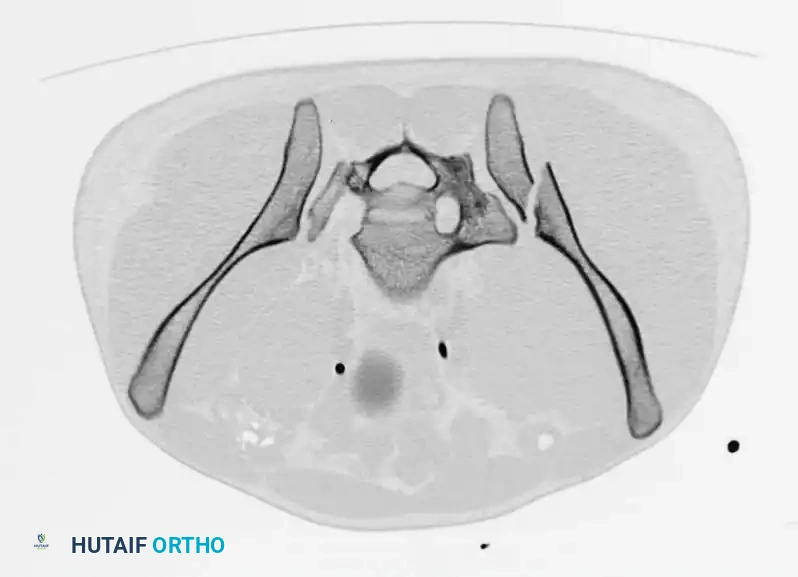

Radiographic Evaluation

Standard evaluation begins with an Anteroposterior (AP) pelvis radiograph. However, definitive surgical planning requires specialized views and advanced imaging.

• Inlet View: Directed 45 degrees caudad. Best evaluates anterior-posterior translation, internal/external rotation, and sacral impaction.

• Outlet View: Directed 45 degrees cephalad. Best evaluates vertical translation and sacral foraminal anatomy.

• CT Scan: The gold standard for evaluating posterior ring injuries, sacral dysmorphism, and preoperative planning for percutaneous fixation.

Image